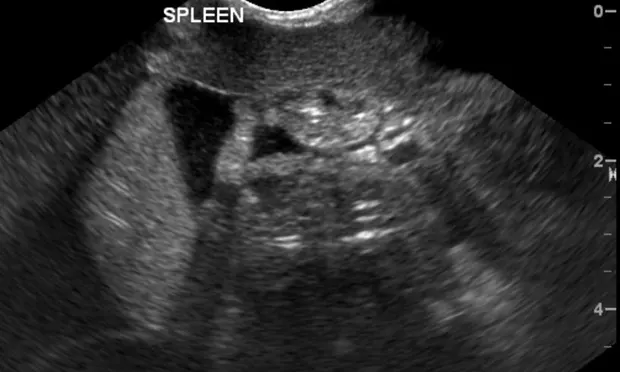

Figure 1: Free abdominal fluid around the spleen visualized with an abdominal FAST examination

An ultrasound image showing the spleen of a veterinary patient, with the organ appearing as a textured structure in shades of gray. The image includes labeled anatomical details, indicating the spleen's position within the abdominal cavity.